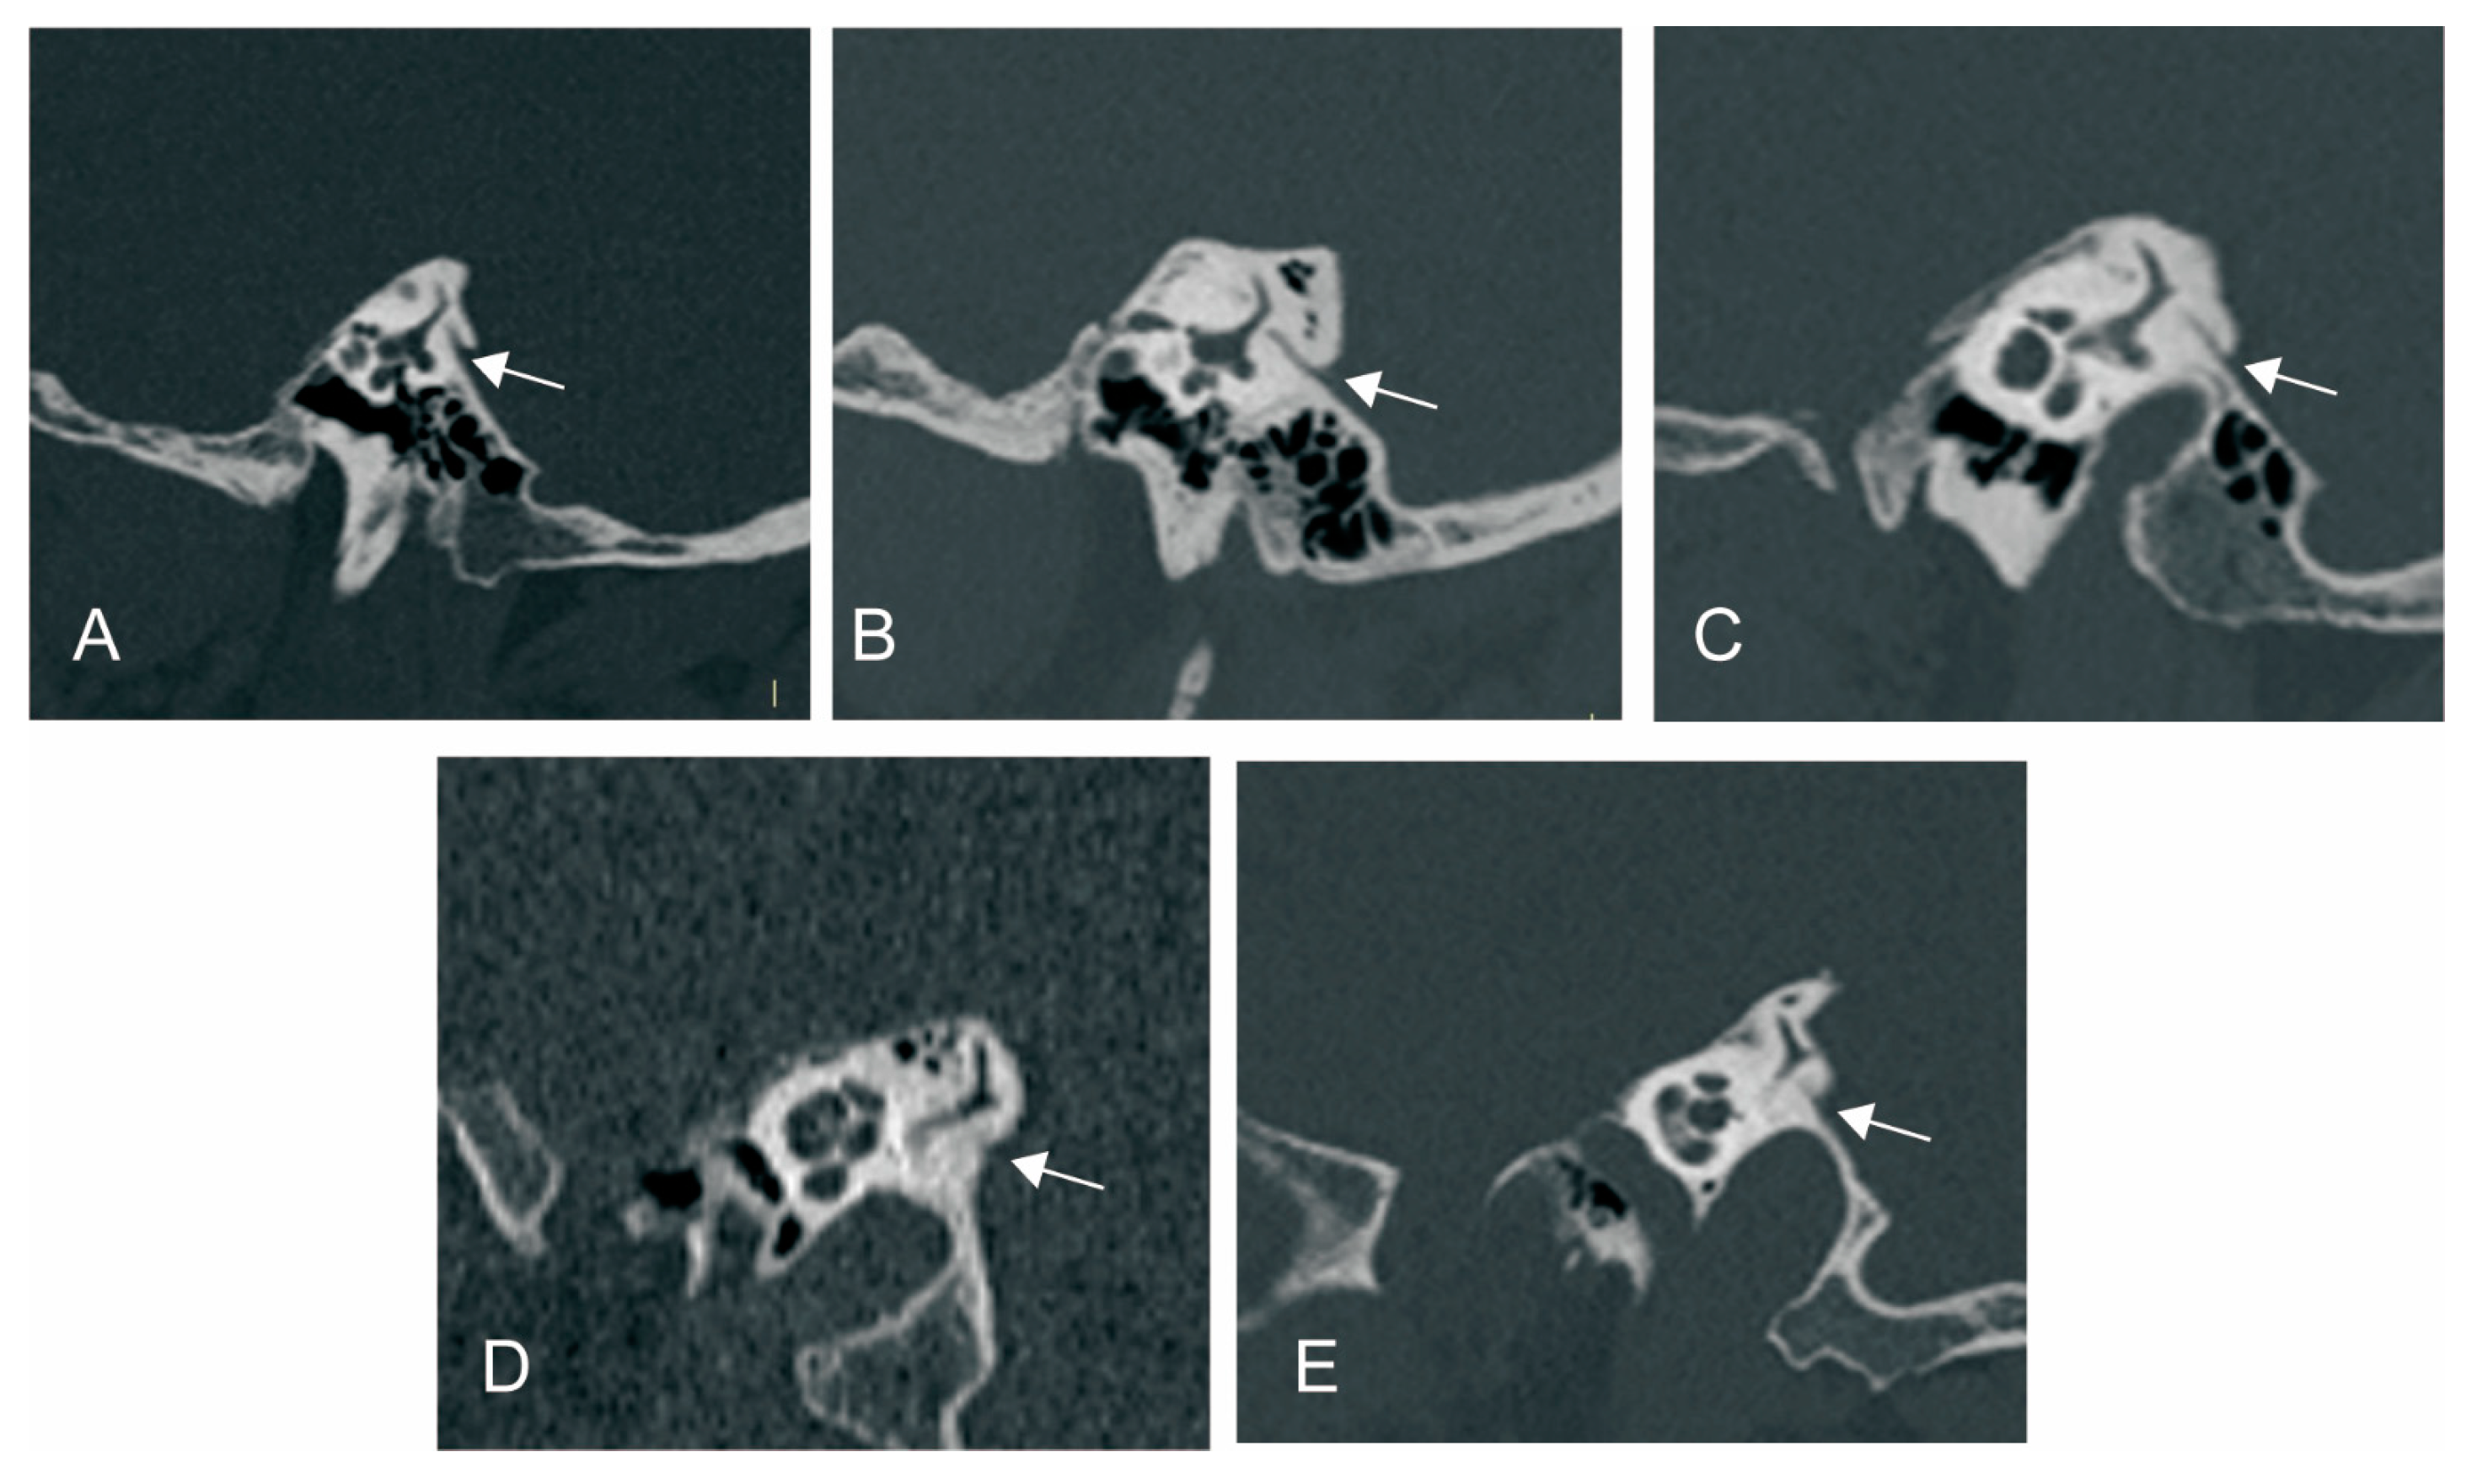

3.2.1. The Relationship between ATVA and VA Visibility and Morphology

3.2.3. The Relationship between ATVA and Peri-VA Pneumatization

2.2.2. Radiological Measurement